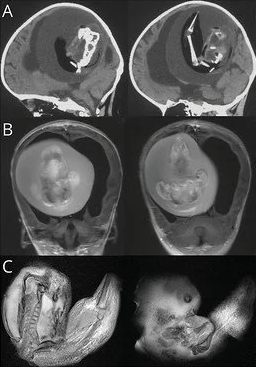

gif_animation 海外SNS上に投稿された、奇跡としか思えない、しかしあまりにも恐ろしい画像。1歳の女の子の脳内で発見された、おそらくは ”双子” として生まれるはずだったと思われる妹、その姿。 世界的にも稀な事例。(※ TOP画はイメージ)[3]images